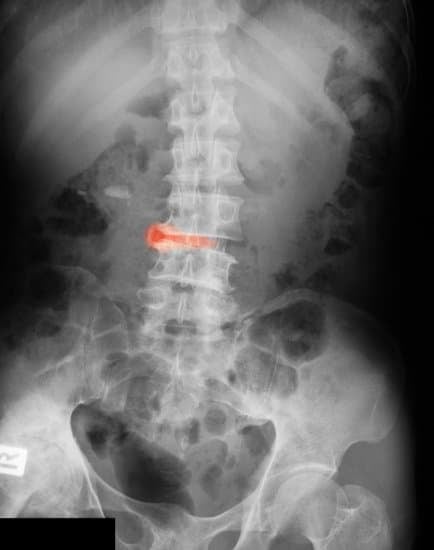

강직성 척추염은 주로 척추와 천장관절(골반과 척추 연결 부위)에 염증이 생겨 점차 굳어지는 만성 염증성 질환입니다.

자가면역 반응으로 인해 척추를 포함한 관절에 염증이 반복적으로 발생하고, 이로 인해 관절이 딱딱하게 유착되고 강직됩니다.

4. 진단 방법

📌 초기에는 영상 검사에서 명확한 소견이 없을 수 있어, 증상과 병력의 조합이 중요합니다.